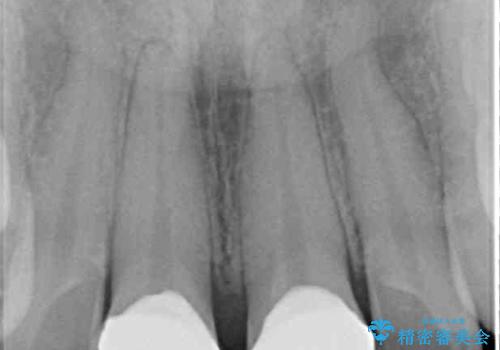

- 上の前歯の隙間を気にして来院された患者様です。

矯正治療により前歯を閉じるという治療を第一選択肢として提案しましたが、期間と費用からオールセラミッククラウンによる補綴治療を行うこととしました。

虫歯もない前歯を削ることは、処置をする者として心苦しいのですが、患者様は矯正治療は選択しないとのことだったので、オールセラミッククラウンにて補綴治療を行いました。

短期間で思い通りの仕上がりとなり、患者様には大変満足していただきました。